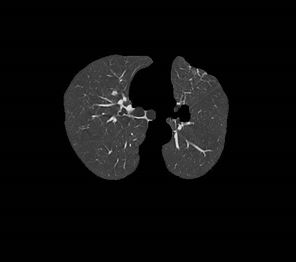

十二、肺部图像数据库联盟(LIDC)

数据下载链接:https://wiki.cancerimagingarchive.net/display/Public/LIDC-IDRI#

数据介绍:肺图像数据库联合会图像收集(LIDC-IDRI)包括诊断性和肺癌筛查性胸部X线断层扫描(CT)扫描,并标明带注释的病变。 它是可通过网络访问的国际资源,用于开发,培训和评估用于肺癌检测和诊断的计算机辅助诊断(CAD)方法。 由美国国立癌症研究所(NCI)发起,并由美国国立卫生研究院(FNIH)基金会进一步推动,并在食品药品监督管理局(FDA)的积极参与下,这种公私合作伙伴关系证明了一项成功的研究成果。

1、肺结节数据库LIDC-IDRI:

CSDN数据库介绍:http://blog.csdn.net/dcxhun3/article/details/54289598

数据库网址:https://wiki.cancerimagingarchive.net/display/Public/LIDC-IDRI

CT Medical Image Analysis Turorial这个比赛好像是分析CT纹理与患者年龄的关系。

肺癌分类比赛:https://www.kaggle.com/c/data-science-bowl-2017/data

分割肺癌(Kaggle):https://www.kaggle.com/kmader/finding-lungs-in-ct-data